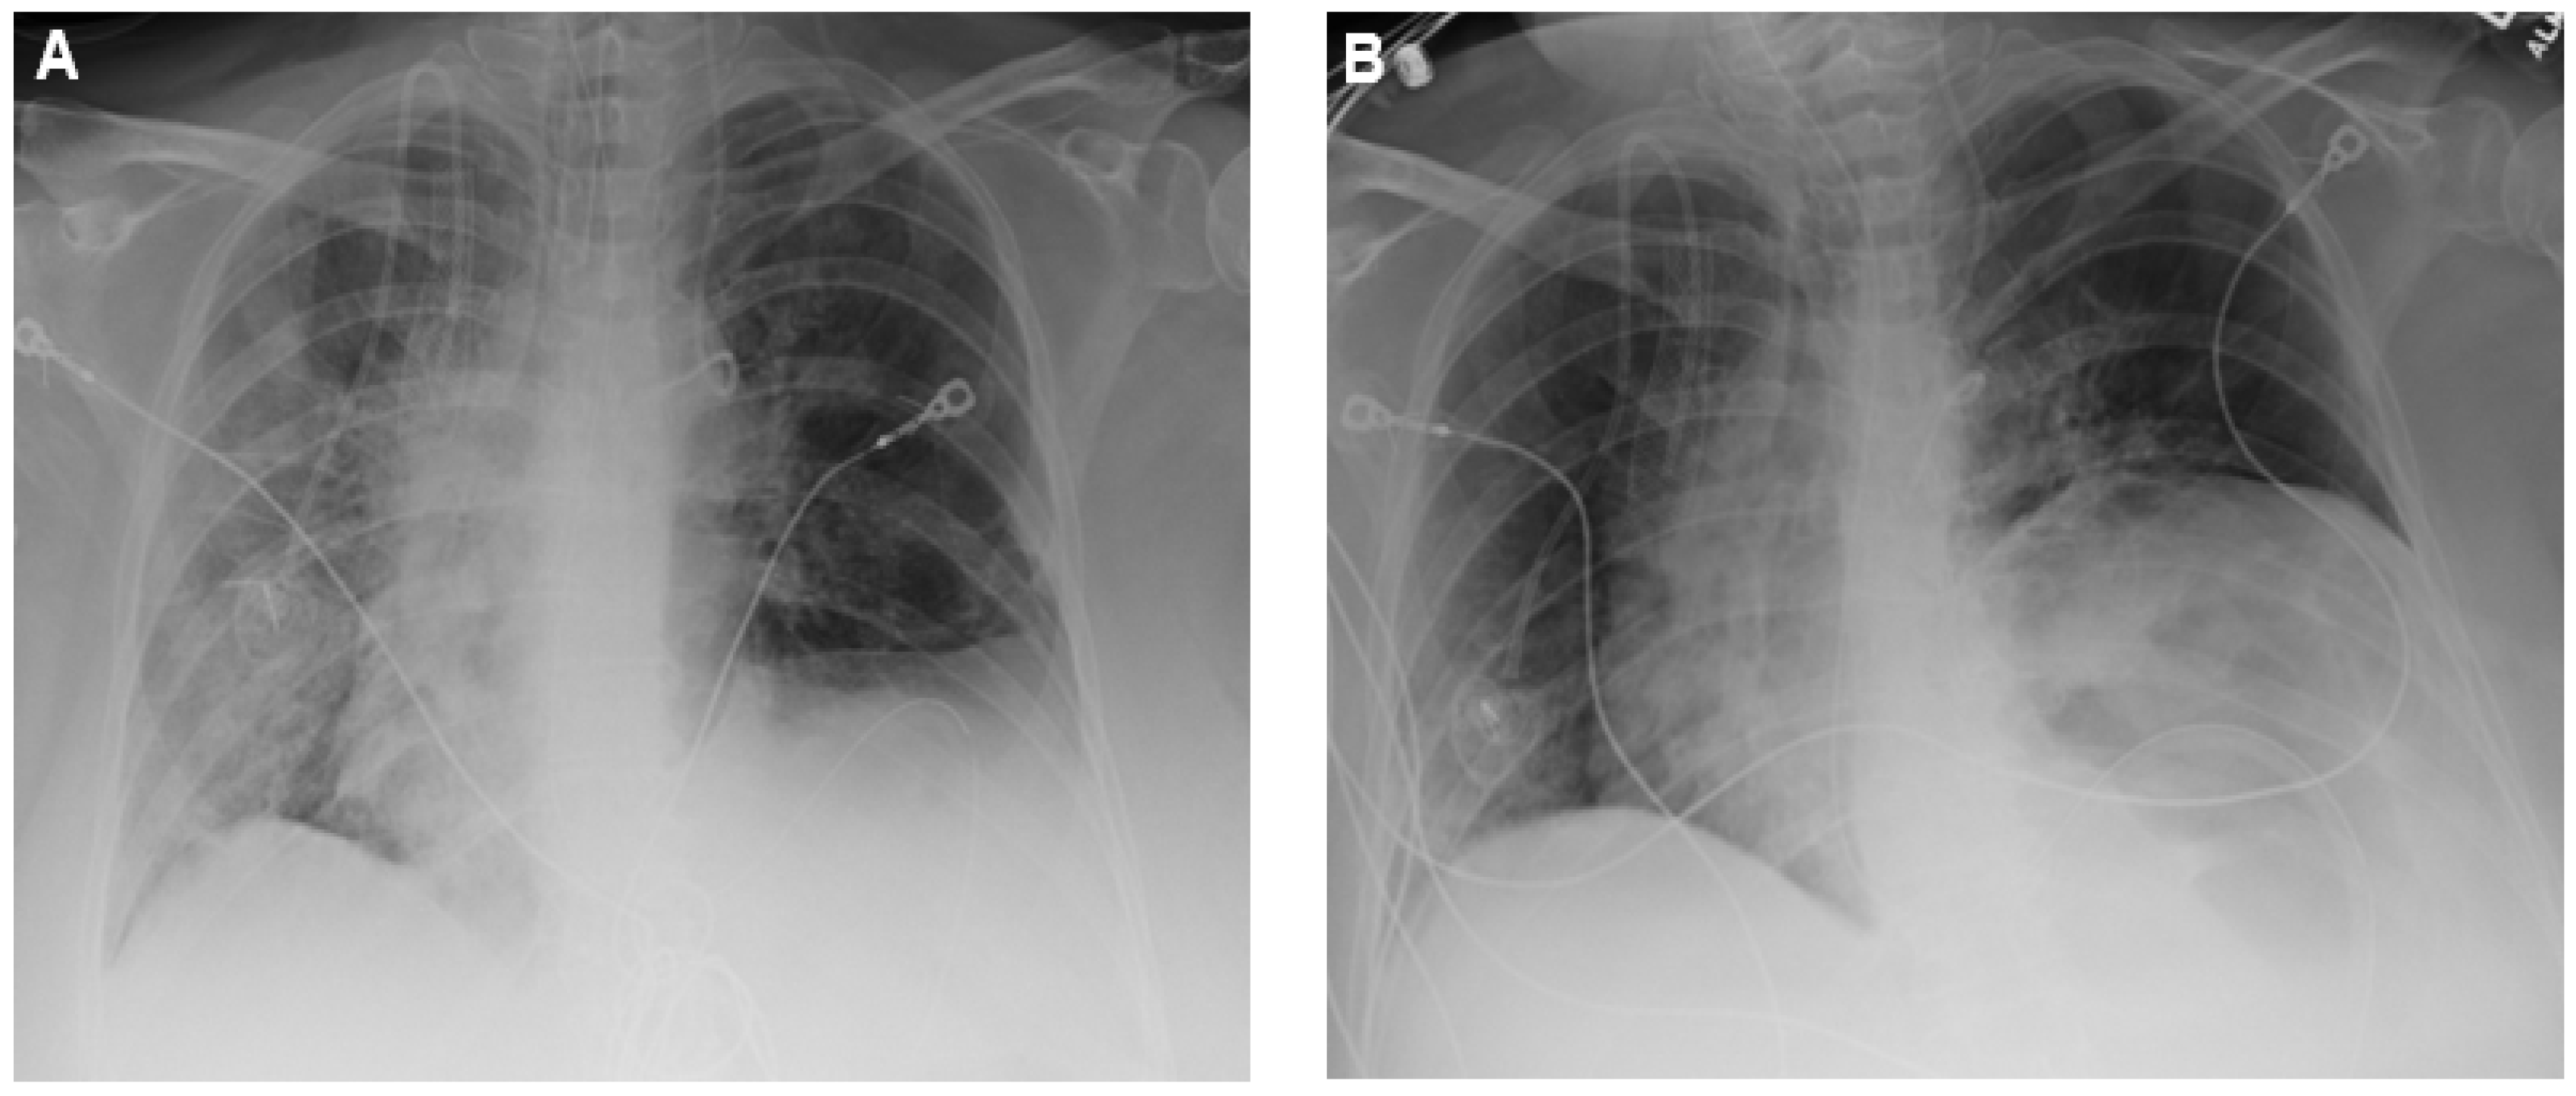

2. Case Presentation